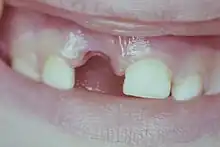

Extrusion

C'est un déplacement partiel de la dent hors de son alvéole. Signes cliniques : dent longue, avec saignement autour de la dent et douleurs spontanées ou provoquées par une simple pression.